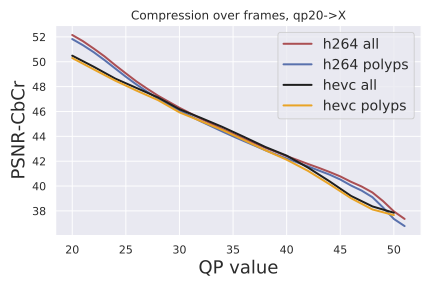

Compression metrics: We evaluate frame quality using two standard image metrics: PSNR-CbCr and PSNR-Y. PSNR is the standard "Peak Signal to Noise Ratio" derived from the mean squared error between pixels in the original frame and the compressed frame. The value of the pixels depends on the type of PSNR computation:“CbCr" corresponds to PSNR between chroma of the frames, and “Y" corresponds to PSNR between luminance of the frames.

Compression quality: Figure 1 (middle) shows the compression rate versus frame quality distribution for H264 and HEVC. Importantly, we see that H264 and HEVC compress the most medically relvant frames statistically significantly worse: treating each QP value separately, a two-sided Kolmogorov-Smirnov test between distribution of PSNR-CbCr shows that the frame quality is lower for polyp frames than for all frames. For each QP value, , , H264 (HEVC) maximum p-value over all tests is (), mean test statistic (). For the same test with PSNR-Y, see the Appendix. Figure 2 top two rows show the lowest quality compressed frames inside the body according to PSNR-CbCr, with and without polyps (for the absolute worst quality compressed frames, see the Appendix).

See Figure 4 for compression quality as a function of QP value instead of compression rate, as well as quality measured by PSNR-Y. Furthermore, the Kolmogorov-Smirnov tests on PSNR-Y show the same behavior: treating each QP value separately, a two-sided between distributions shows that the frame quality is lower for polyp frames than for all frames (for each QP value, , , H264 PSNR-Y max p-value is , mean test statistic , HEVC PSNR-Y maximum p-value over all tests is , mean test statistic ). This result holds for each QP value between 20 and 51.